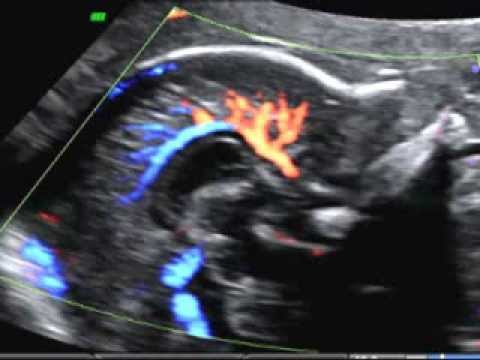

Hellow guys, Welcome to my website, and you are watching Excision of Callosal Marginal Dissecting Aneurysm With End-to-End Anastomosis. and this vIdeo is uploaded by NEUROSURGERY Journal at 2018-02-27T09:18:25-08:00. We are pramote this video only for entertainment and educational perpose only. So, I hop you like our website.